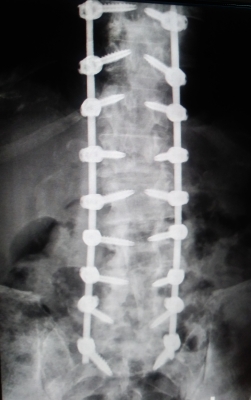

What They Took Out! Reinstalled - From S1 to T10